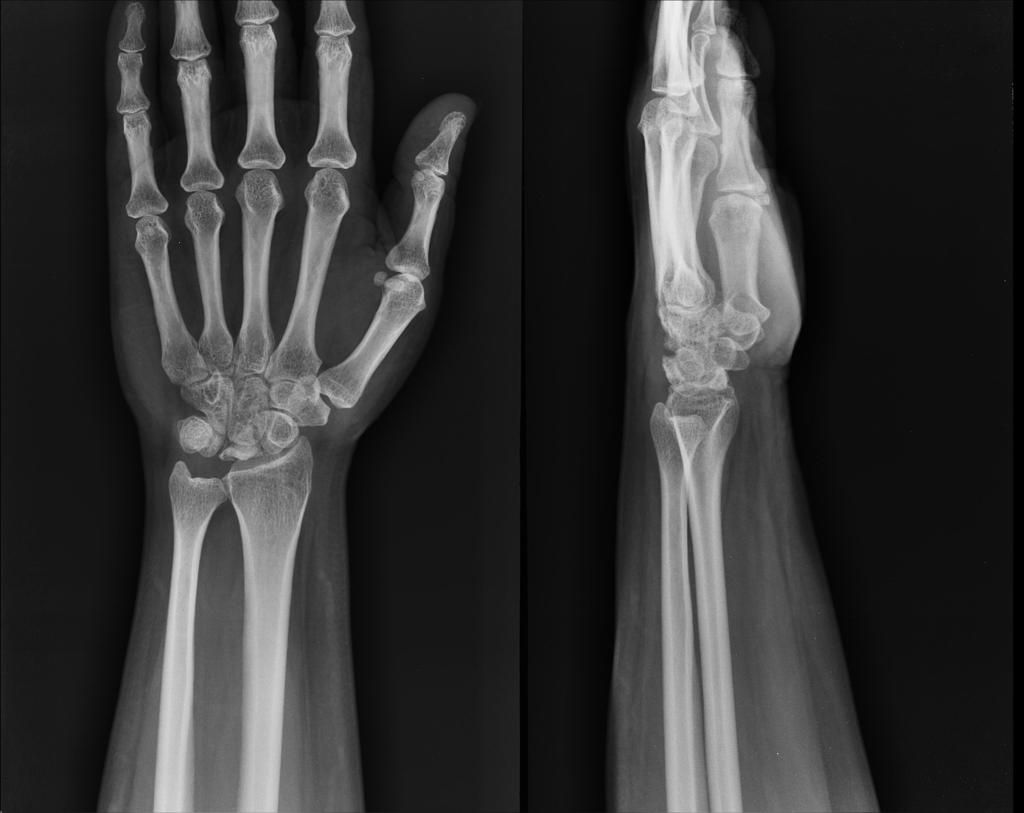

Kienbock’s Disease, also known as avascular necrosis of the lunate bone, is a progressive wrist condition that can significantly affect hand function. ROBERT KIENBOCK, in 1910, described what he called “TRAUMATIC SOFTENING” of the lunate bone. This is a form of ischemic necrosis that usually follows chronic stress or injury.

Kienbock’s Disease is a disorder characterised by the loss of blood supply to the lunate, one of the key carpal bones in the wrist. This leads to bone death (avascular necrosis), resulting in pain, stiffness, decrease grip strength, and long-term wrist disorder.